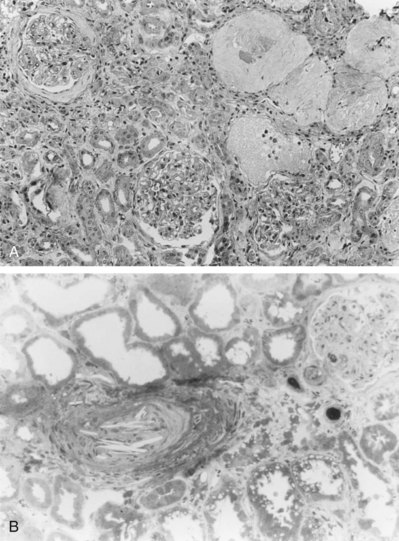

Primary intimal fibroplasia occurs in children and in young adults and constitutes approximately 10% of the total number of fibrous lesions. This lesion is characterized by a circumferential accumulation of collagen inside the internal elastic lamina (Fig. 39–2). Disruption and duplication of the elastica interna occur more often in younger patients, with dissecting hematomas as a complication in many patients. The possibility of atherosclerosis as a cause of renal artery disease in this group can be excluded histologically by the absence of lipid demonstrable with special staining techniques. Intimal fibroplasia with complicating medial dissection is characterized pathologically by large dissecting channels in the outer half of the media. These lesions are thought to develop because of defects in the internal elastica with resultant medial dissection and aneurysmal dilatation.

Figure 39–2 A, Photomicrograph of a cross section demonstrates intimal fibroplasia with focal fragmentation and partial absence of the elastica interna. B, Photomicrograph of cross section demonstrates severe renal arterial intimal fibroplasia with a dense cuff of intimal collagen apposed to the luminal surface of a partially disrupted elastica interna. A small recannulized channel is noted in the lower left.

(From Novick AC. Renal vascular hypertension in children. In: Kelalis PP, King LR, Belman AB, editors. Clinical pediatric urology. Philadelphia: WB Saunders; 1984.)